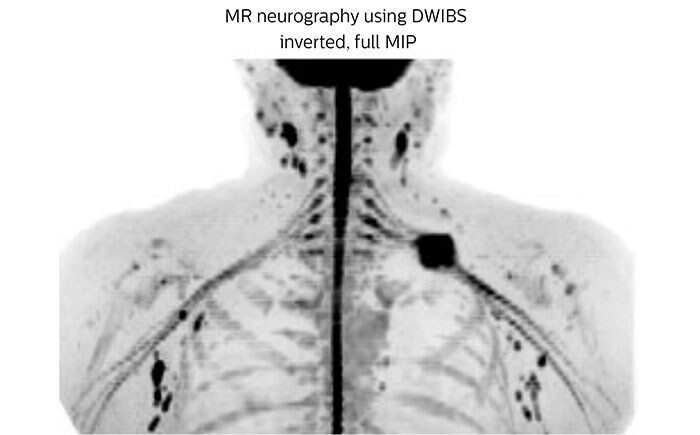

This patient is a 43-year-old female with a left supraclavicular nerve sheath tumor. The lesion is well visualized on the STIR VISTA images and on the MR neurography using DWIBS. The exam was performed on Prodiva 1.5T.

Acq voxel size 1.2 x 1.3 x 2.4 mm, Recon voxel size 0.7 x 0.7 x 1.2 mm, dS SENSE factor 2, scan time 5:46 min.